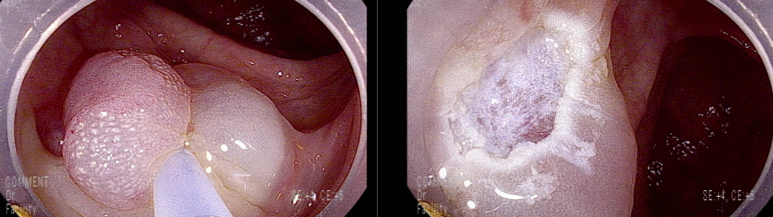

마지막 유경성 거대 용종을 제외하고 점막 소구 패턴(pit pattern)이 불규칙하게 관찰되어(Vi) 고등급의 선종 혹은 점막암을 의심하여 충분히 융기시켜 경계가 확실히 포함되고 한조각으로 완전 절제하기 위해 넓게 절제함

7-8 mm 크기

9 mm 크기